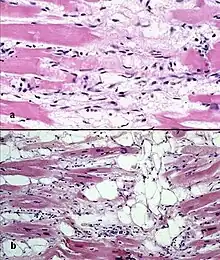

| Typical micro-histologic features of ARVC/D. Ongoing myocyte death (upper) with early fibrosis and adipocyte infiltration (lower). | |

There are two pathological patterns seen in ACM, Fatty infiltration and fibro-fatty infiltration.

Fatty infiltration

At first, fatty infiltration, is confined to the right ventricle. This involves a partial or near-complete substitution of myocardium with fatty tissue without wall thinning. It involves predominantly the apical and infundibular regions of the RV. The left ventricle and ventricular septum are usually spared. No inflammatory infiltrates are seen in fatty infiltration. There is evidence of myocyte (myocardial cell) degeneration and death seen in 50% of cases of fatty infiltration.

Fibro-fatty infiltration

The second, fibro-fatty infiltration, involves replacement of myocytes with fibrofatty tissue. A patchy myocarditis is involved in up to 2/3 of cases, with inflammatory infiltrates (mostly T cells) seen on microscopy. Myocardial atrophy is due to injury and apoptosis. This leads to thinning of the RV free wall (to < 3 mm thickness) Myocytes are replaced with fibrofatty tissue. The regions preferentially involved include the RV inflow tract, the RV outflow tract, and the RV apex. However, the LV free wall may be involved in some cases. Involvement of the ventricular septum is rare. The areas involved are prone to aneurysm formation.

A biopsy sample that is consistent with ACM would have > 3% fat, >40% fibrous tissue, and <45% myocytes.

A post mortem histological demonstration of full thickness substitution of the RV myocardium by fatty or fibro-fatty tissue is consistent with ACM.